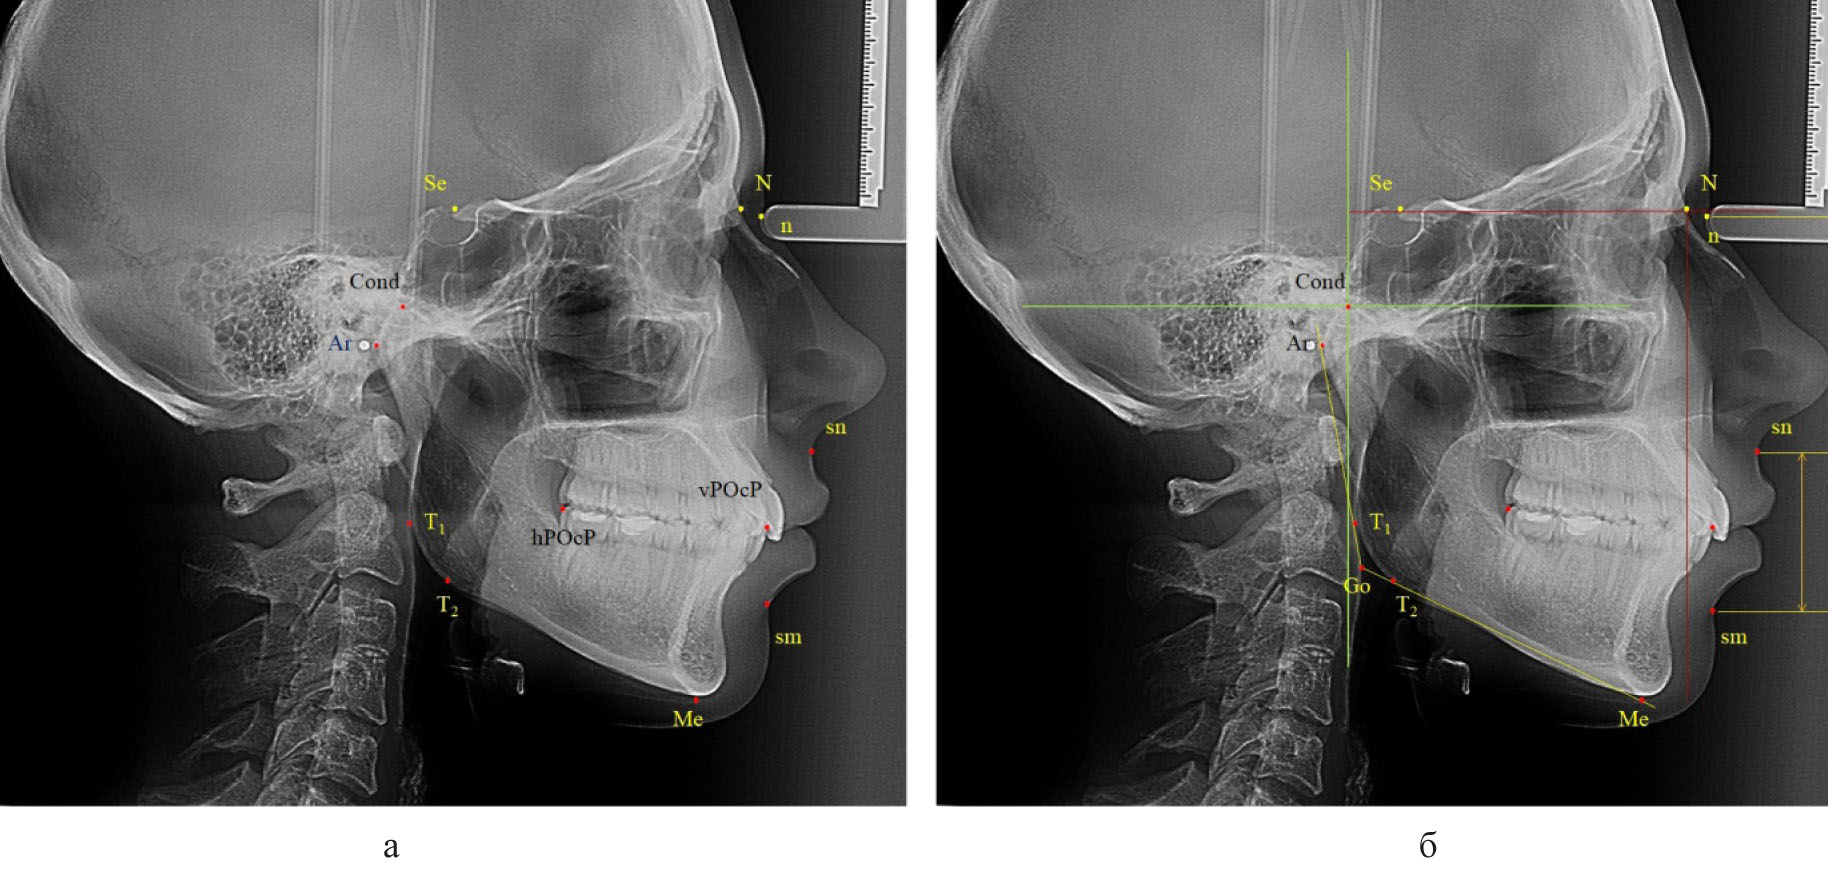

Для оценки типа роста использовали наиболее удобный показатель, такой как угол нижней челюсти. Основные точки для построения угла были наиболее выступающие части ветви, обозначаемые литерами (Ar) и (T1), и тела челюсти (T2) и (Me). Линии, соединяющие отмеченные точки, определяли угол нижней челюсти и положение конструктивной точки «Go» (рис. 2).

Рис. 2. Точки (а) и линии (б) для анализа угла нижней челюсти

Нейтральный тип роста и нижнечелюстного угла определялся при его величине от 119 до 123 градусов. Увеличение размеров свидетельствовало о принадлежности к вертикальному типу, а уменьшение – к горизонтальному типу.